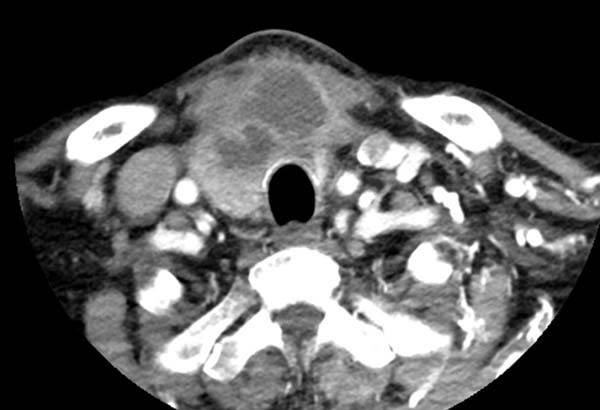

头臂干压迫左头臂静脉

左侧锁骨下静脉受主动脉弓挤压,

导致对比剂冲入浅表静脉网中

左侧锁骨下静脉受主动脉弓挤压 血管充盈不佳